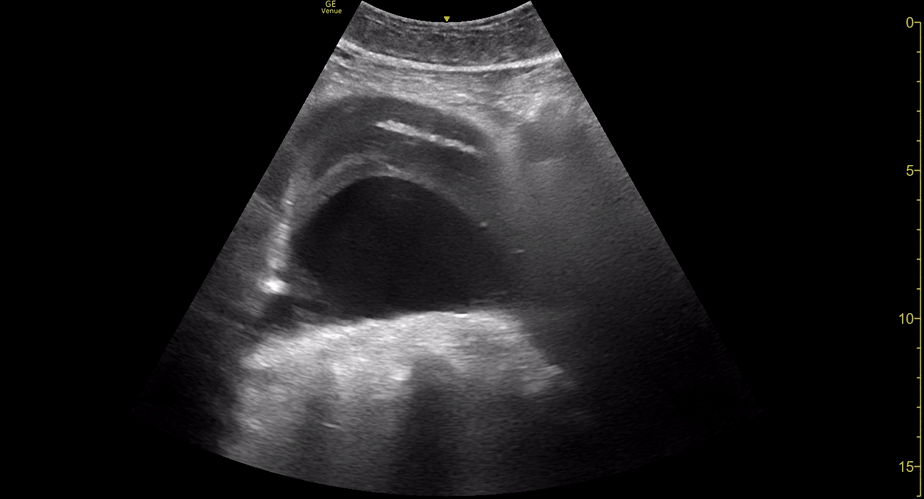

AAA

AAA GALLERY

AORTIC ANEURYSM

In adults, the normal anteroposterior aortic diameter is less than 2 cm, and 3 cm or more is considered dilated. The diameter of the common iliac arteries should not be more than 1.5 cm. Most AAAs occur below the renal arteries. As an aneurysm becomes larger it will dilate faster, leading to a greater risk of rupture. This risk remains low if the diameter is less than 5 cm. By contrast, there is a clear tipping point after surpassing 5.5 cm, as the annual incidence of rupture grows from <1% to 9.4% (5)

Once the aorta is identified, measure its diameter from outer to outer wall, as inner wall measurements may underestimate the diameter due to mural thrombus (false negative). While maintaining the transverse orientation, slide the probe distally until the aortic bifurcation and measure the diameter at its middle and distal portions. Then, rotate the probe to the longitudinal position, which is needed to identify saccular aneurysms. Attempt to obtain a view of the aorta that includes the origin of the coeliac trunk or SMA, and measure the AP diameter. Remember, AAA is not ruled out unless the entire length of the abdominal aorta can be visualized and measured.